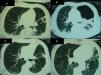

Achados radiológicos obtidos durante o internamento do doente. Tomografia computadorizada (TC) do tórax, demonstrando: (A) (quarta semana de internamento) condensação bilateral alveolar com derrame pleural, e aspergiloma no hemitórax esquerdo; (B) (nona semana após internamento) hidropneumotórax; (C e D) (6 meses após internamento) melhoria do derrame pleural e do hidropneumotórax. O aspergiloma foi removido durante a cirurgia.

A endoscopia digestiva alta confirmou o diagnóstico de candidíase esofágica. Passadas 2 semanas, suspendeu-se o tratamento com fluconazol, e após 21 d de tratamento com cotrimoxazol, este foi ajustado para 960mg qd, e a prednisolona reduzida para 10mg qd. A avaliação laboratorial do sangue periférico revelou uma contagem de linfócitos T CD4+ de 21 células/μl (5%) e uma carga viral de VIH-1 de 307 285 cópias/ml. Foi observada melhoria clínica parcial com o tratamento instituído, persistindo a febre. À quarta semana de internamento, foi realizada uma tomografia computadorizada (TC) do tórax, que revelou uma condensação bilateral alveolar com derrame pleural, e uma cavidade com sinal do halo, no pulmão esquerdo (fig. 1). O doente foi submetido a broncofibroscopia com colheita de lavado broncoalveolar (LBA 1). Foi observada uma alta carga de quistos de Pneumocystis jirovecii (4-30 por campo, com ampliação x1 000), através da técnica de imunofluorescência indireta com anticorpos monoclonais (IF) (kit MonoFluo P. jirovecii, Bio-Rad, França). A presença de P. jirovecii foi confirmada por amplificação do gene que codifica para a subunidade grande do rRNA mitocondrial (mtLSU rRNA), utilizando PCR nested. No mesmo LBA, foi observado o crescimento de Aspergillus fumigatus em cultura. Após conhecimento destes resultados, a terapêutica antimicrobiana foi alterada para clindamicina (600mg qid), primaquina (30mg qd) e voriconazol (200mg após uma dose de carga). Devido à persistência da febre, foi pesquisada a presença de antigenémia pp6 do citomegalovírus (CMV), que foi positiva (248 células infetadas/50 000 leucócitos). Contudo, na fundoscopia, exame do líquido cefalorraquidiano, endoscopia digestiva alta e colonoscopia não se encontraram alterações atribuíveis ao CMV. No entanto, no LBA foi encontrado DNA de CMV por PCR, pelo que se iniciou ganciclovir (325mg b.i.d.). Foram cumpridos 26 d de clindamicina e primaquina, e 21 d de ganciclovir. Posteriormente, foram iniciadas as profilaxias com atovaquona (1 500mg qd), pirimetamina (50mg qd), e valganciclovir (900mg qd).

Uma semana depois, o doente desenvolveu um hidropneumotórax à esquerda. Foi submetido a descorticação pleural com toracotomia, e remoção do aspergiloma (fig. 1). No tecido removido, continuaram a ser identificados P. jirovecii e A. fumigatus. Duas mutações, nos codões 75 e 78 do gene DHPS de P. jirovecii, foram detetadas pela primeira vez (GenBank: números de acesso GU479992, GU479993), verificando-se a presença de uma treonina em vez de uma isoleucina na posição 75da proteína, e de uma prolina em vez de uma leucina na posição 78. Os resultados da genotipagem de P. jirovecii no tecido pleural e nas secções de aspergiloma estão resumidos na tabela 1.